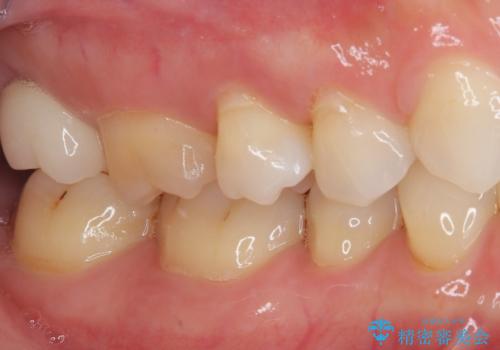

根管治療を行った奥歯は、再発防止や残された歯質を守るため、クラウンによる補綴治療が必要となります。

補綴後6ヶ月経過しレントゲンを撮影したところ、根尖周辺の病変が消失していることが確認できました。